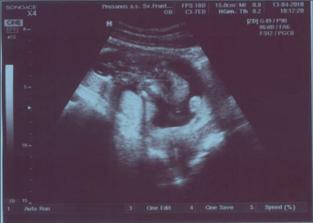

# 13.4. o 9.30 - Maminka sa snažila (a celkom úspešne) vypiť denne aspoň jednu fľašu vody. V práci sa mi podarí vypiť 1,5 litrovku a doma ešte pár pohárov, ale potom len behám na záchod :D... a práve preto naše bábätko rastie "ako z vody." O necelé 2 týždne narástlo 3cm! Už začína mať menej priestoru, čo dobre vidno na fotkách, ani na UTZ sa už celé nezmestí. Konečne som aj ja videla malé priamo na ultrazvuku, vačšinou mi doktorka dá len fotku, ale dnes otočila monitor tak, aby mi mohla povysvetľovať. A zase pár slzičiek utieklo. Veľká radosť!